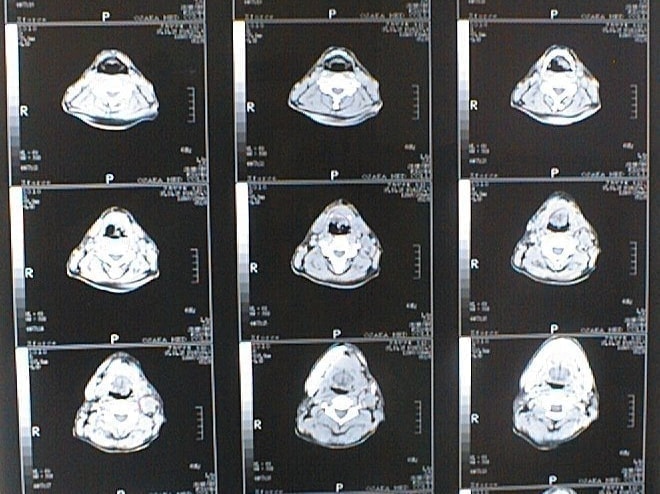

末期がん宣告時と末期がん消滅時の診断画像比較

ここでは、末期がんと宣告された時のCT&MRI画像と、その約3か月後の末期がん消滅時の画像を比較して頂けます。(写真左が「末期がん宣告時の画像」、写真右が「末期がん消滅後の画像」)

CT画像比較

入院当時CT画像①

入院3か月後癌消滅CT画像①

入院当時CT画像②

入院3か月後癌消滅CT画像②

入院当時CT画像③

入院3か月後癌消滅CT画像③